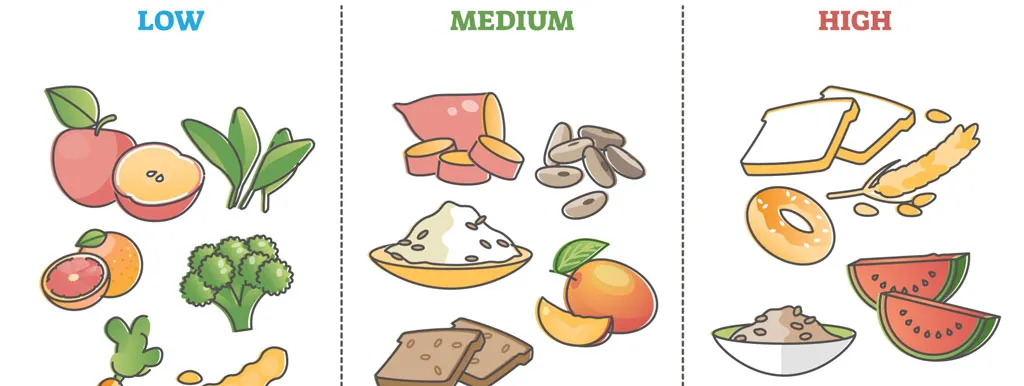

Glykemische index is een eigenschap van voeding: de mate waarin 50 gram koolhydraat uit voeding de bloedglucose verhoogt in vergelijking met 50 gram glucose. Glucosepieken geven opstootjes van oxidatieve stress en kunnen op lange termijn insulinresistentie veroorzaken.

In 'glykemische lading' zit ook de effectieve inname van koolhydraten vervat (glykemische index × gewicht koolhydraat). Een gelijkaardig resultaat werd verkregen door glykemische lading als parameter te nemen.